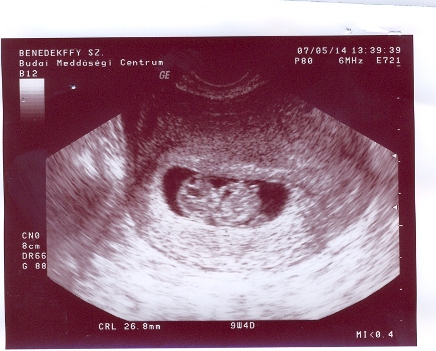

Nem tüntem el, csak időm nincs a 2 gyerek mellett. Mi lesz ha meg lesz a 3.

Benszi!

Nagyon jók az Uh képek. Én most nem kaptam, de ezek után se fogok kapni, mert videóra vesszük majd fel, másik 2 fiam is így van megörökítve.